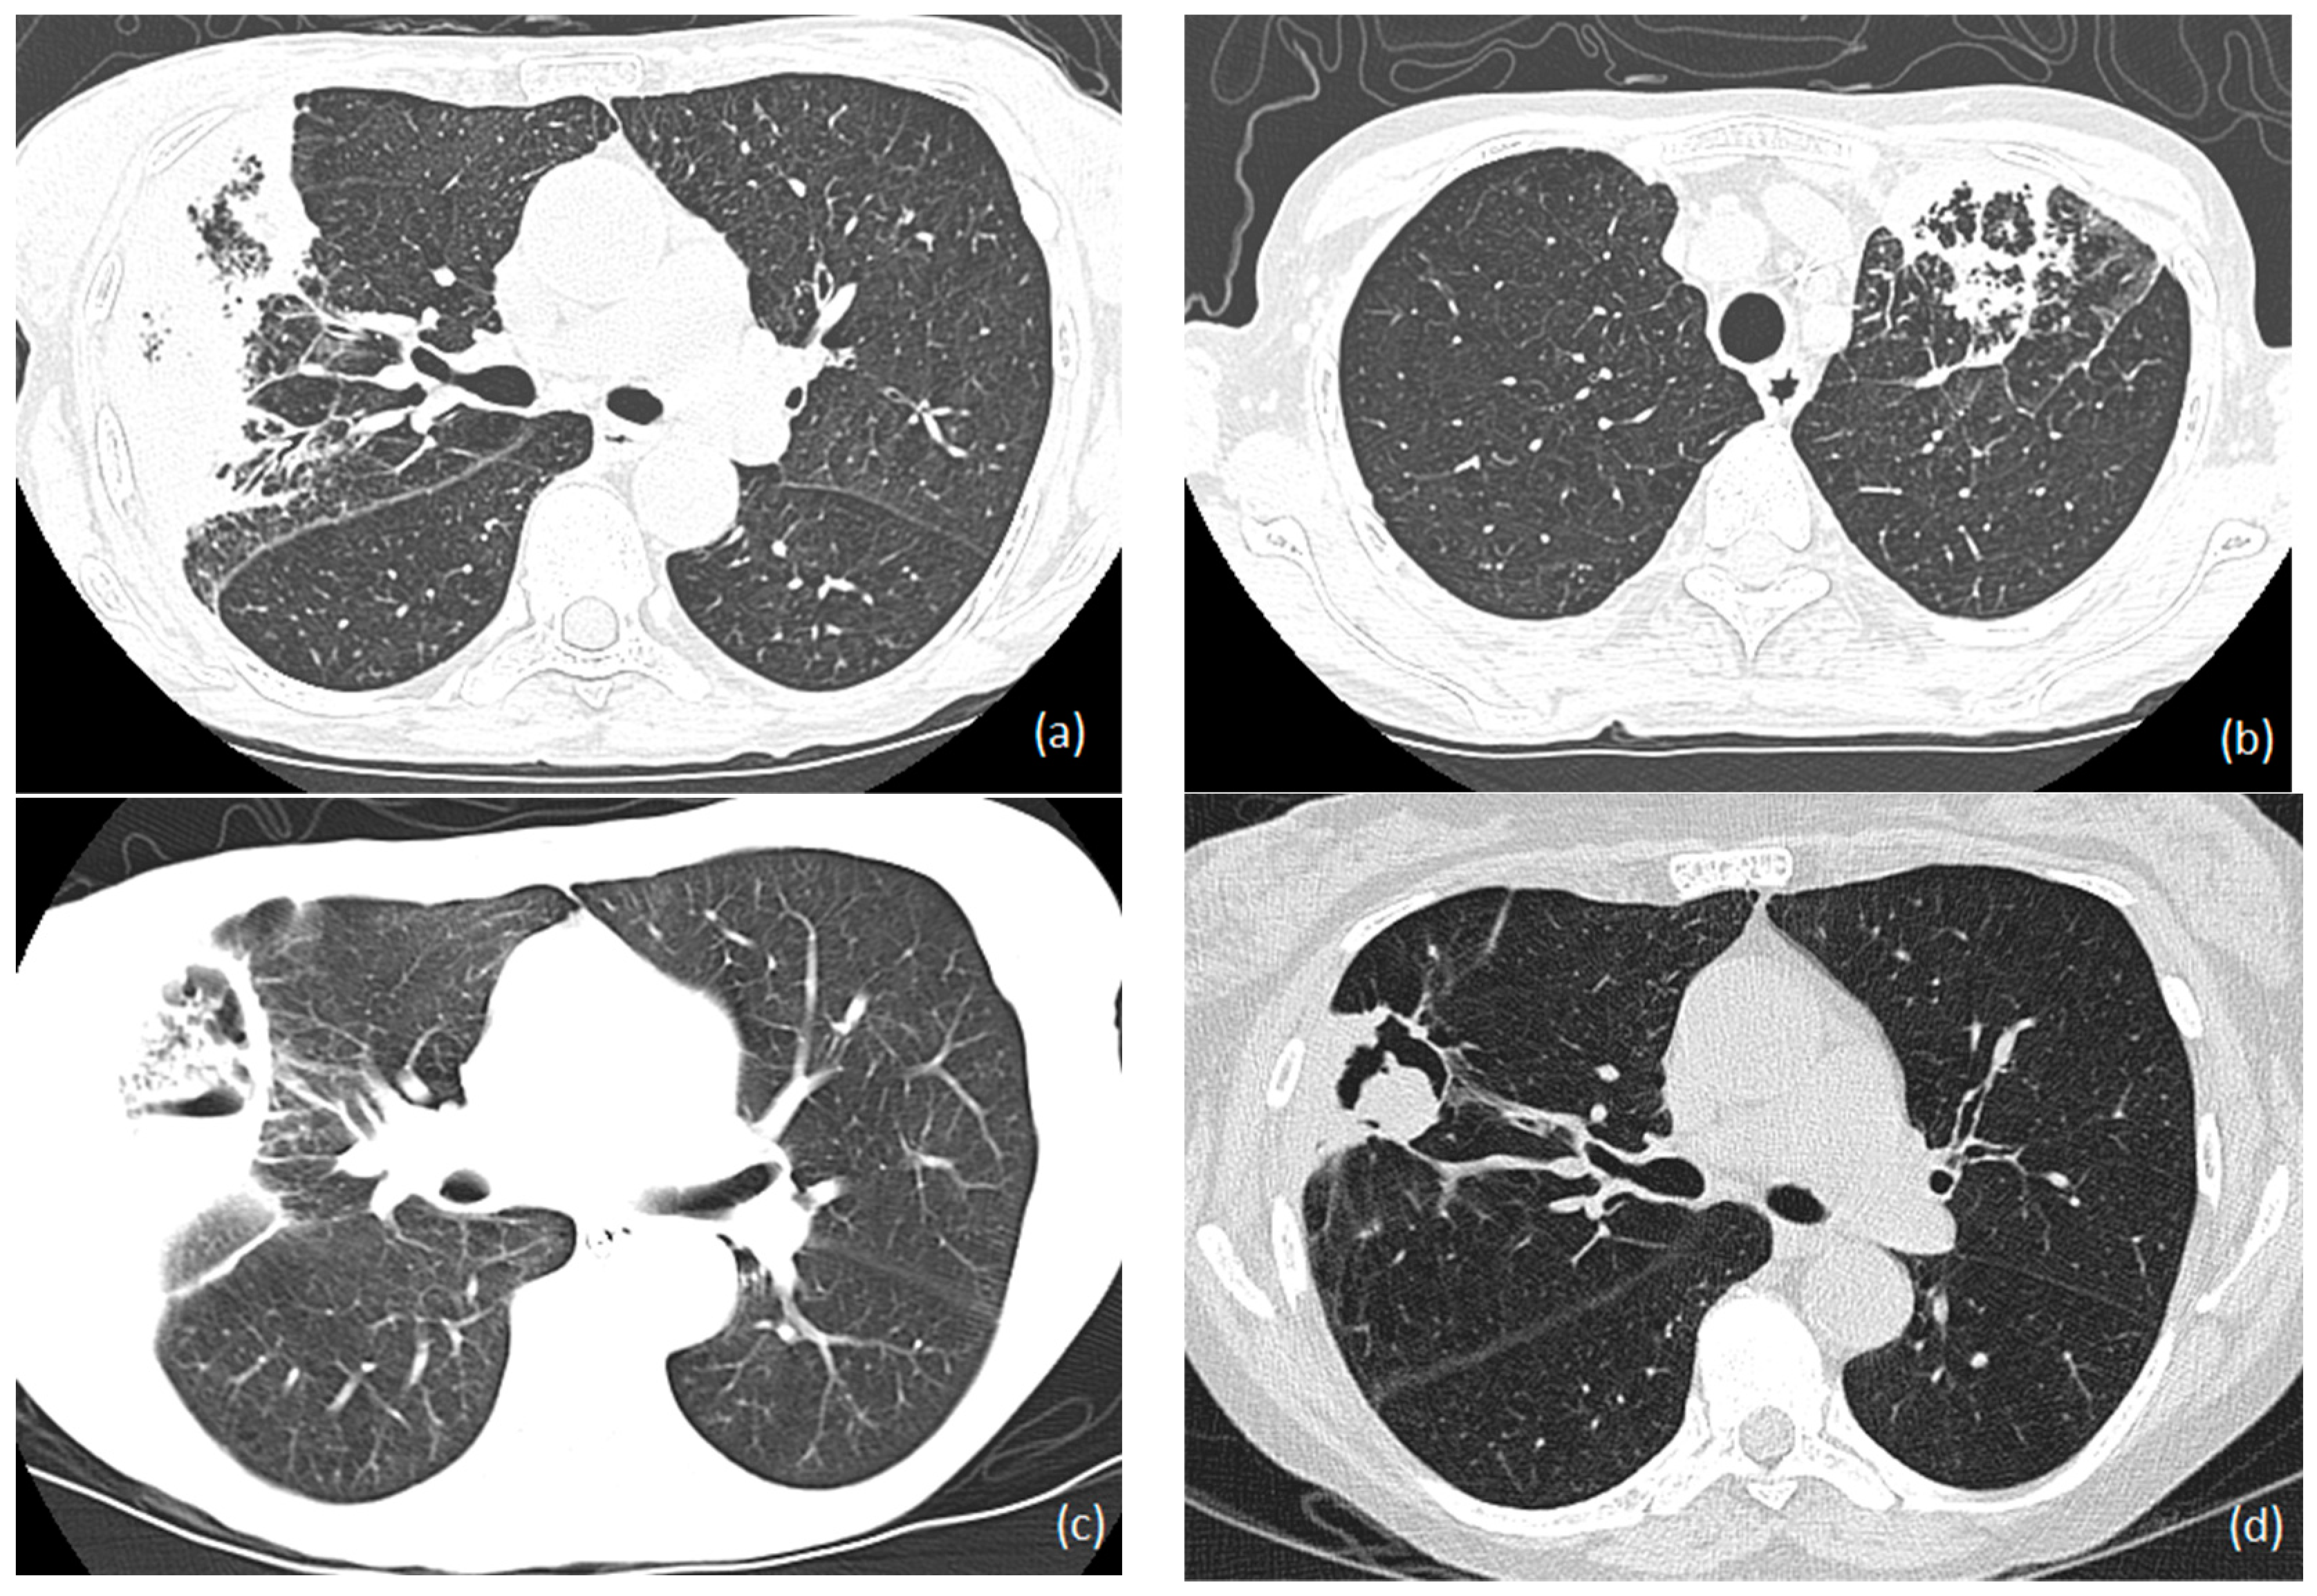

1.6.4. Radiology